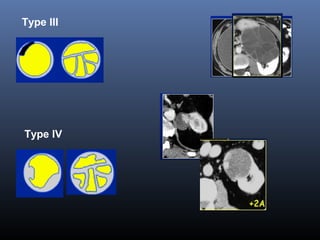

Phân lo i BosniakạType I Nang đ n thu nơ ầ :

Đ m đ d ch(-10-20 UH), đ ng d ng,gh rõ, không th y v ,không b tậ ộ ị ồ ạ ấ ỏ ắ

thu c c n quangố ả

=> Lành tính, không c n theo dõiầ

Type II Nang không đi n hìnhể :

vài vách m ng, vài đ m vôi v , đ m đ d ch cao(> 50UH)ỏ ố ở ỏ ậ ộ ị

Không b t thu c c n quang (<10UH)ắ ố ả

=> Lành tính , không c n theo dõiầ

Type II F (follow-up) Nang không đi n hình nhi uể ề

=> C n theo dõiầ

Type III Nang nghi ng :ờ

Nhi u vách d y+/hay thành nang d y, gi i h n không đ uề ầ ầ ớ ạ ề

Các vôi d y +/hay không đ u, đ m đ d ch cao (>20UH)ầ ề ậ ộ ị

Thành và vách b t thu c c n quangắ ố ả

+> ph u thu t sinh thi tẫ ậ ế

Type IV Ung th u th n (d ng nang)ư ậ ạ

Thành nang d y, không đ u -Có ch i, sùi , các n tầ ề ồ ố

Vách nang và các ch i, n t b t thu c c n quang (>50UH)ồ ố ắ ố ả

=> Ph u thu t c t th nẫ ậ ắ ậ

Phân lo i c a Bosniakạ ủ